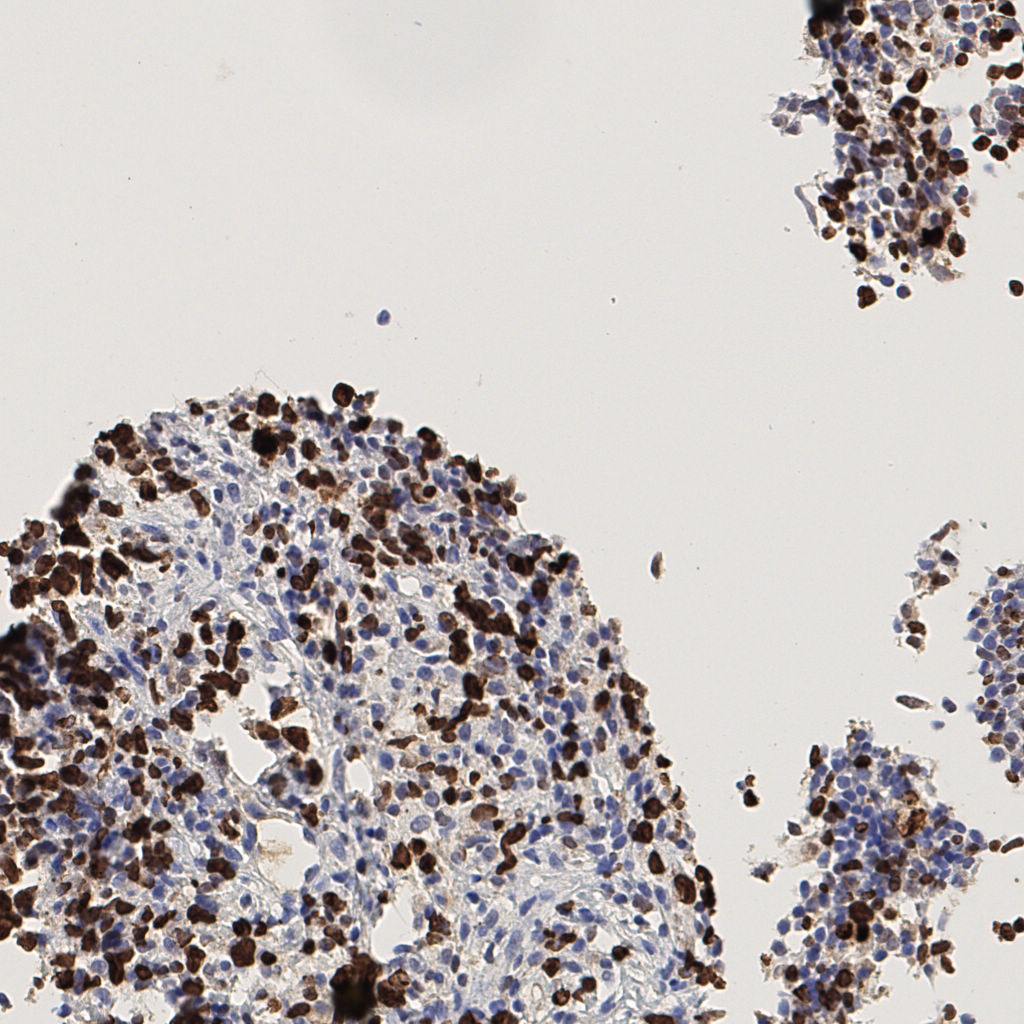

7.85%

Ki67 指数

阴 1104 阳 94

H255858-KI-67.ndpi